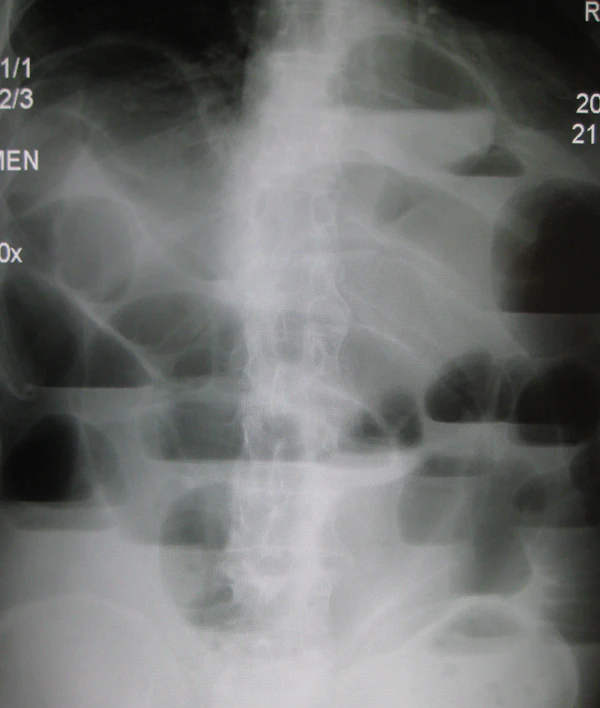

Чаши Клойбера

Чáши Клóйбера — патогномоничный (специфический для конкретной патологии и только для неё) рентгенологический симптом кишечной непроходимости. Обусловлен наличием раздутых участков кишки, наполненных частично жидкостью, частично газом. Проявляется картиной «перевёрнутых чаш» с горизонтальным уровнем жидкости на снимке брюшной полости при вертикальном положении пациента[1][2].